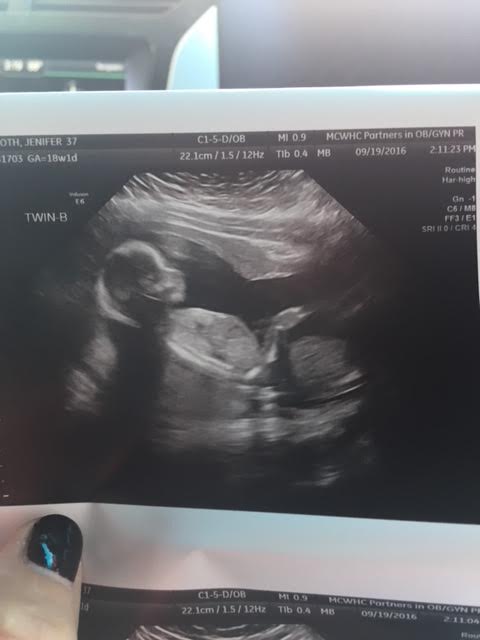

Ultrasound Photos at 18 Weeks Pregnant With Twins